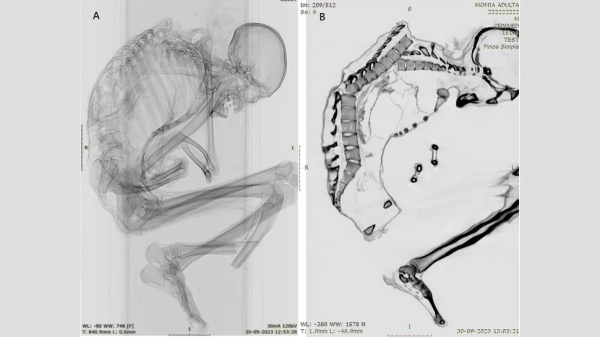

Каталина Моралес и Франсиско Гарридо, археологи из Национального музея естественной истории в Сантьяго, использовали компьютерную томографию и рентгеновские снимки, чтобы выявить мельчайшие детали обширной травмы, которая, вероятно, привела к смерти мужчины. Они сообщили:

По словам ученых, на верхней части позвоночника мужчины были обнаружены многочисленные незажившие переломы. У него также были переломы ребер, лопатки и ключицы, что указывает на «сильный удар по обширной области» верхней части спины, показывая, что «верхняя левая часть грудной клетки приняла на себя основной удар». Удар сместил несколько позвонков и разрушил грудную клетку.

Кроме того, исследователи обнаружили перелом у основания позвоночника, который был результатом первоначальной травмы верхней части спины. Они написали:

Важно, что на черепе, шее и руках мужчины не было обнаружено никаких повреждений, что указывает на то, что удар произошел, когда мужчина находился в положении головой вниз. Возможно, он активно занимался добычей полезных ископаемых или пытался защитить голову руками, когда на него упал тяжелый предмет сверху. Подобные травмы наблюдаются у людей, пострадавших от землетрясений, а также при производственных травмах в лесной, строительной и горнодобывающей промышленности.